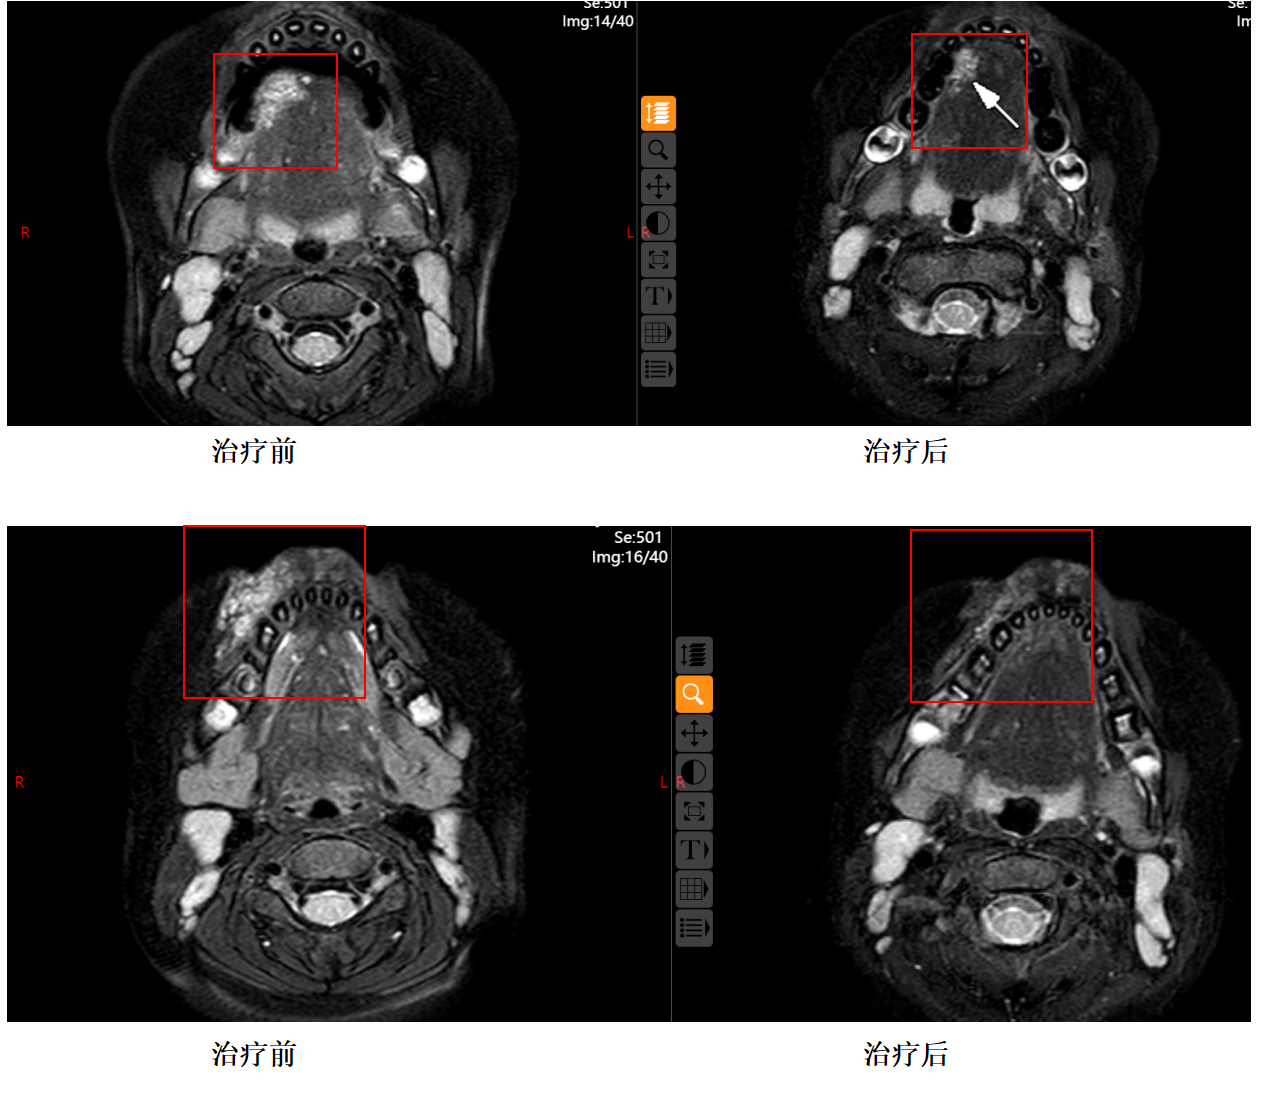

按照手术排期,1个月后,患儿来门诊做好核酸,术前检查后入院,第二天就安排入介入室行介入治疗。孩子全麻下,很顺利的进行了动脉造影、药物灌注、影像引导下硬化治疗等一系列介入手术治疗,术后第一天就平安回家了。因为患儿病灶部位在口腔部且病灶部位相对较大,在确保安全、美观的基础上对患儿进行疗程化治疗。

三、术后复查

孩子再次来时,包块比上次已经缩小很多,影像学也验证了临床的改善,相信再经过一段时间恢复,孩子就可以痊愈了!